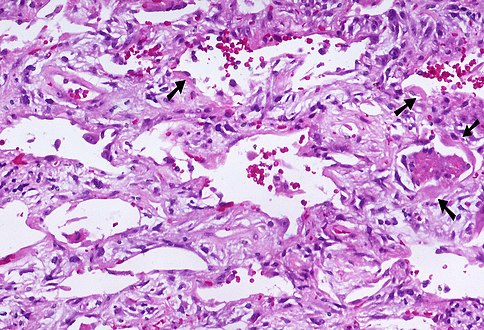

Hyaline membranes - very high mag.jpg

Micrograph of diffuse alveolar damage, the histologic correlate of acute interstitial pneumonitis. H&E stain.

Rapid progression from initial symptoms to respiratory failure is a key feature. An X-ray that shows ARDS is necessary for diagnosis (fluid in the small air sacs (alveoli) in both lungs). In addition, a biopsy of the lung that shows organizing diffuse alveolar damage is required for diagnosis. This type of alveolar damage can be attributed to nonconcentrated and nonlocalized alveoli damage, marked alveolar septal edema with inflammatory cell infiltration, fibroblast proliferation, occasional hyaline membranes, and thickening of the alveolar walls. The septa are lined with atypical, hyperplastic type II pneumocytes, thus leading to the collapse of airspaces. Other diagnostic tests are useful in excluding other similar conditions, but history, X-ray, and biopsy are essential. These other tests may include basic blood work, blood cultures, and bronchoalveolar lavage.[citation needed] The clinical picture is similar to ARDS, but AIP differs from ARDS in that the cause for AIP is not known.